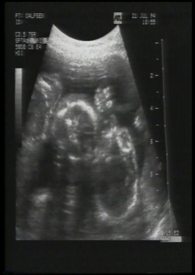

我们总期待着新生命的降临,但却从不知道那来到身旁的,表象为人类的肉块容器中,真的是装着我们所期待的..

我们总期待着新生命的降临,但却从不知道那来到身旁的,表象为人类的肉块容器中,真的是装着我们所期待的未来吗?

我们是否有权利决定或主导它的一切?